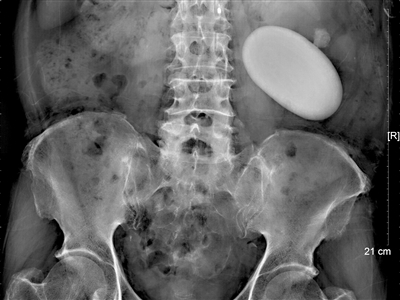

肾里长巨石块头超鹅蛋

他把白大褂上的口袋缝死;三鹿奶粉事件爆发前,他通过b超发现数十例"肾